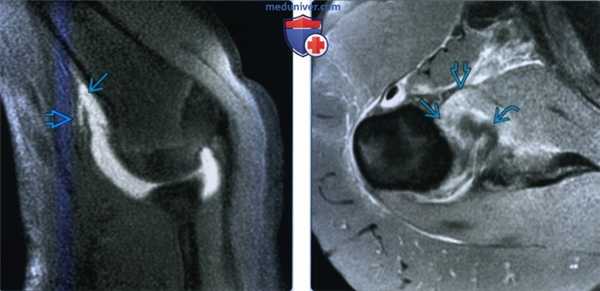

(Слева) На рисунке с повреждением в виде отрыва суставно-плечевой связки от плечевой кости показан передний пучок нижней суставно-плечевой связки, который разорван около прикрепления к плечевой кости. Разрыв направляется кзади к подмышечному карману нижней суставно-плечевой связки.

(Справа) На фронтальной косой МР-артрограмме Т2 FS определяется симптом J повреждения в виде отрыва суставной связки от плечевой кости. Нижняя суставно-плечевая связка оторвана от места прикрепления к плечевой кости, что приводит к ее свисанию в виде буквы J. Суставная жидкость вытекла через постоянный разрыв связки у пациента с нестабильностью после предшествующего вывиха.

о Симптом J: разорванная латеральная часть нижней суставно-плечевой связки свисает вниз на фронтальных изображениях: - Нормальная интактная нижняя суставно-плечевая связка в форме буквы U приобретает форму буквы J

о МР-артрография

(Слева) МР-артрография в режиме Т2ВИ FS, коронарный срез: визуализируются изменения, соответствующие отрыву переднего пучка НСПС. Связка разорвана в области прикрепления к плечевой костив. Культя связки вследствие ретракции имеет волнистый контур и напоминает букву «J». Область прикрепления НСПС к суставной впадине лопатки не изменена.

(Справа) МР-артрография в режиме Т1ВИ FS, аксиальный срез: отмечается отслаивание переднего пучка НСПС от плечевой кости. Связка медиальнее разрыва утолщена. Передненижняя суставная губа интактна. (Слева) МР-артрография в режиме Т1ВИ FS, аксиальный срез: визуализируется отрыв заднего пучка НСПС, возникший после вывиха плеча. Наблюдается распространение контрастного препарата в мягкие ткани через дефект в заднем пучке НСПС.